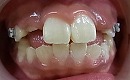

開咬とは写真の様に奥歯しか咬んでいない咬み合わせの事を言います。

初診日 18歳7か月 女子

終了日 20歳1か月(治療期間2年1か月)